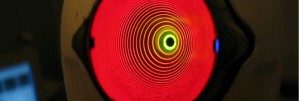

anelli intrastrominali anestesia angio oct atrofia del nervo ottico avastin cataratta Cheratocono chirurgia delle vie lacrimali chirurgia refrattiva chirurgia vitreo retinica corsoecm Dacriocistorinostomia degenerazione maculare senile edema maculare Endoscopia nasale epiretiniche Femtolaser foro maculare intervento di cataratta ipermetropia laser ad eccimeri laser a diodi Laser a femtosecondi laser argon laser yag macula malattie retiniche miopia OCT oftalmopatia tiroidea PRK ptosi palpebrale pucker pucker maculare puker maculare retina retinopatia diabetica retrazione palpebrale simposio oculistico sindrome interfaccia vitreo retinica trattamenti anti-aging trombosi venosa retinica vie lacrimali vitrectomia vitreopatia